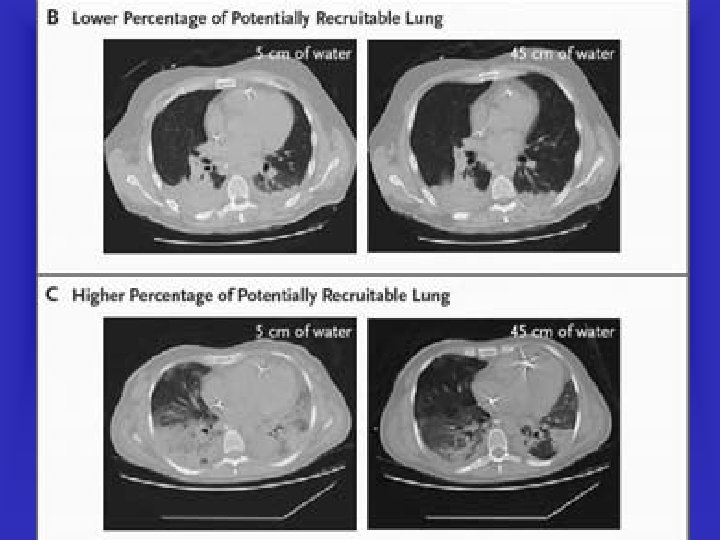

Mortality according to % of recruitable lung